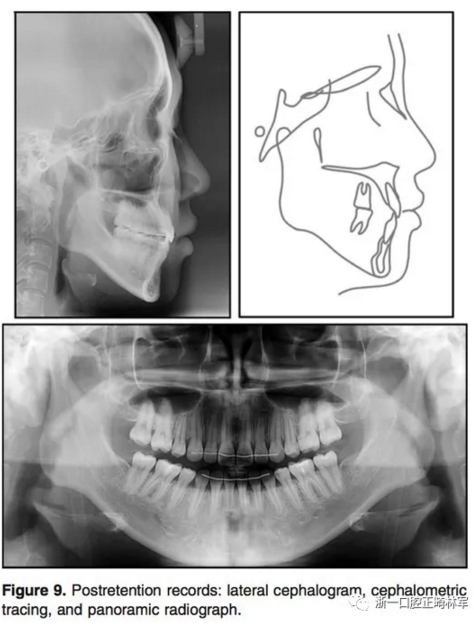

治療后結(jié)果示,治療目標(biāo)達(dá)成。側(cè)貌改善。唇可以完全閉合,獲得了美學(xué)微笑(圖5)。全景示間隙關(guān)閉,牙根平行度可,未見明顯吸收。側(cè)位片分析和重疊像分析示上前后牙分別壓入2.8mm和1.9mm。下前后牙分別壓入4.2mm和1.4mm。上下頜前牙用最大支抗內(nèi)收。雙牙弓壓入后,下頜發(fā)生了逆時(shí)針旋轉(zhuǎn)(2.1°)??和頦前點(diǎn)前移(3mm)。

6.jpg